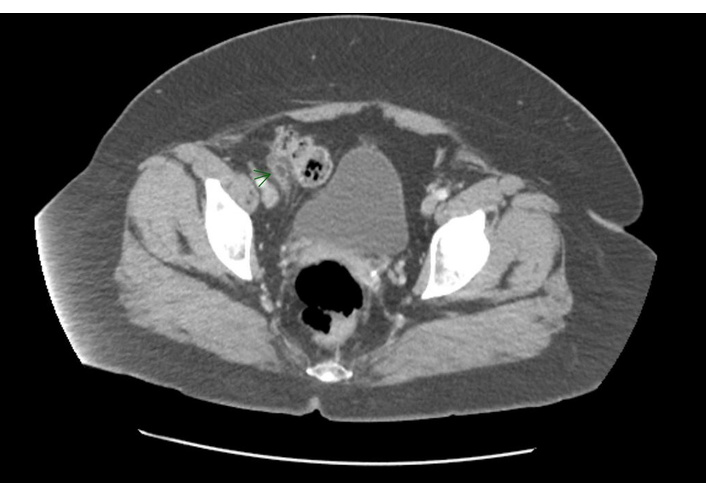

Physical examination demonstrated focal right lower quadrant tenderness. The patient denied fever or dietary changes prior to the start of the abdominal pain. Initial clinical suspicion included constipation and appendicitis. A bowel regimen was initiated but did not improve symptoms, and the patient reported progressive abdominal pain exacerbated by movement, coughing, and car travel. Due to persistent symptoms and concern for appendicitis, a computed tomography (CT) of the abdomen and pelvis with contrast was obtained (Figure 1). The images from the CT scan confirmed epiploic appendagitis at the level of the cecum.

Contrast-enhanced computed tomography (CT) of the abdomen/pelvis. Contrast-enhanced CT of the abdomen/pelvis demonstrating an ovoid fat-density lesion adjacent to the cecum with surrounding inflammatory change, consistent with epiploic appendagitis. The normal caliber of the appendix and absence of appendiceal enlargement, and periappendiceal fluid reduce suspicion for appendicitis and support epiploic appendagitis as the primary diagnosis.

The CT demonstrated an ovoid fat-density lesion lateral to the cecum with surrounding focal fat stranding and a hyperattenuating ring, consistent with epiploic appendagitis. The appendix was visualized and appeared normal. No ascites, peritoneal fluid collections, intraperitoneal air, abdominal wall hernia, colonic wall thickening, pericolonic inflammatory changes, or findings suggestive of active colitis or terminal ileitis were noted. Lesion size was not documented in the imaging report. The radiologist’s impression was “Epiploic appendagitis at the level of the cecum. Normal appendix”.

Appendicitis was the primary diagnostic concern given the patient’s right lower quadrant pain and progressive symptoms. Other potential etiologies included constipation, diverticulitis, inflammatory bowel syndrome flare, and epiploic appendagitis. CT imaging demonstrated a focal fat density lesion with a hyperattenuating rim adjacent to the cecum and a normal appearing appendix, findings consistent with epiploic appendagitis and excluding appendicitis.